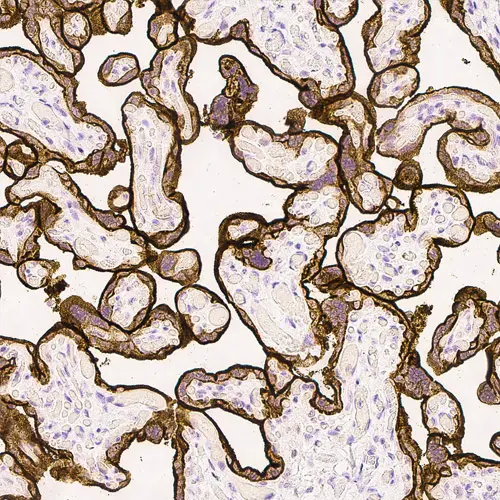

T cell lymphoma: immunohistochemical staining for CD7. Note the intense membrane staining of tumor cells. CD7: clone LP15

The CD7 molecule is a membrane-bound glycoprotein of 40 kD and is the earliest T cell specific antigen to be expressed in lymphocytes. CD7 antigen is also the only early marker to persist throughout differentiation. The function and role of the CD7 molecule have not yet been fully identified, although the activation of T cells with gamma/delta receptors has been proposed based on mAb-induced activation. The CD7 antigen is reported to be found on the majority of peripheral blood T cells, most natural killer cells and thymocytes.